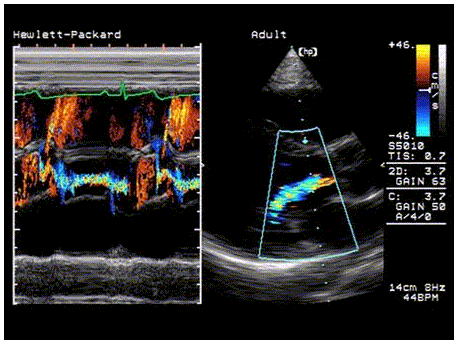

Herz Ultraschall mit Doppler

Bei der Ultraschall-Untersuchung des Herzens  ermöglicht das Doppler-Verfahren den Nachweis von Herzklappenfehlern und Blutfluss- und Druckverhältnisse im Herzen.

Mit Hilfe der Herzsonographie erhält der Arzt Aufschluss über die Struktur von Herzwänden und Herzklappen, deren Bewegungsabläufe, über die Wanddicke von Herzvorhöfen und Herzkammern, über die Größe der Herzinnenräume und der gesamten Herzgröße sowie über die Auswurfleistung des Herzens (diese wird als Herz-Minuten-Volumen bestimmt).